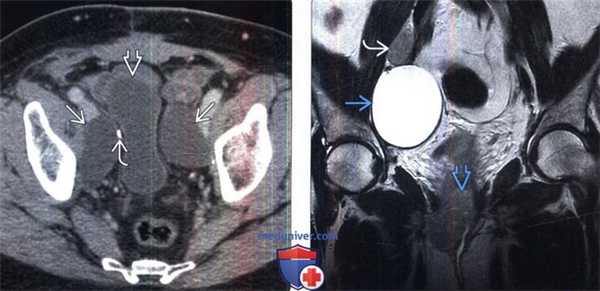

(Слева) КТ с КУ, аксиальная проекция. Двусторонние лимфоцеле ЖЖ у пациента, которому ранее выполнялась тиреоидэктомия по поводу рака щитовидной железы. Клипсы, оставшиеся после лимфодиссекции, указывают на то, что пациенту ранее выполнялось оперативное лечение, а повреждение лимфатического протока имеет ятрогенную природу.

(Справа) МРТ Т1ВИ, коронарная проекция. Спонтанное лимфоцеле, однородное и дольчатое по структуре, сигнал жидкостной. Лимфоцеле располагается в правой надключичной ямке, над местом слияния подключичной и внутренней яремной вен.

(Слева) КТ с контрастированием, аксиальная проекция: после простатэктомии выявлена компрессия мочевого пузыря двусторонним лимфоцеле. Обратите внимание на хирургическую клемму от лимфодиссекции.

(Справа) МРТ, Т2-ВИ, SS FSE, коронарная проекция: после гистерэктомии и лимфодиссекции по поводу рака шейки матки выявлено ограниченное лимфоцеле с высокой ИС на Т2-ВИ. Обратите внимание на рецидив первичной опухоли и прилегающий к уретре и метастаз в лимфатическом узле.